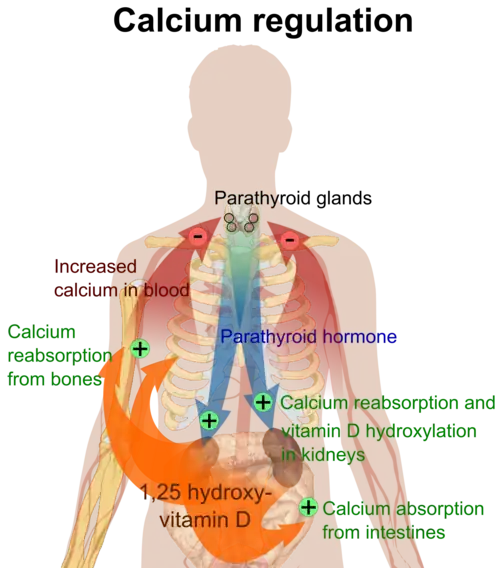

Parathyroid hormone is responsible for the induction of increased calcium absorption in the gastrointestinal tract or gut and in the kidney. It also induces calcium and phosphate resorption from the bone by osteoclasts.[15][11] Parathyroid hormone also plays a role in activating vitamin D from its pro form to its active form.[15] Vitamin D is also responsible for increased blood calcium levels and works in conjunction with parathyroid hormone. Vitamin D is also partly responsible for the inhibition of parathyroid hormone release by binding Vitamin D receptors at the parathyroid gland.[11]